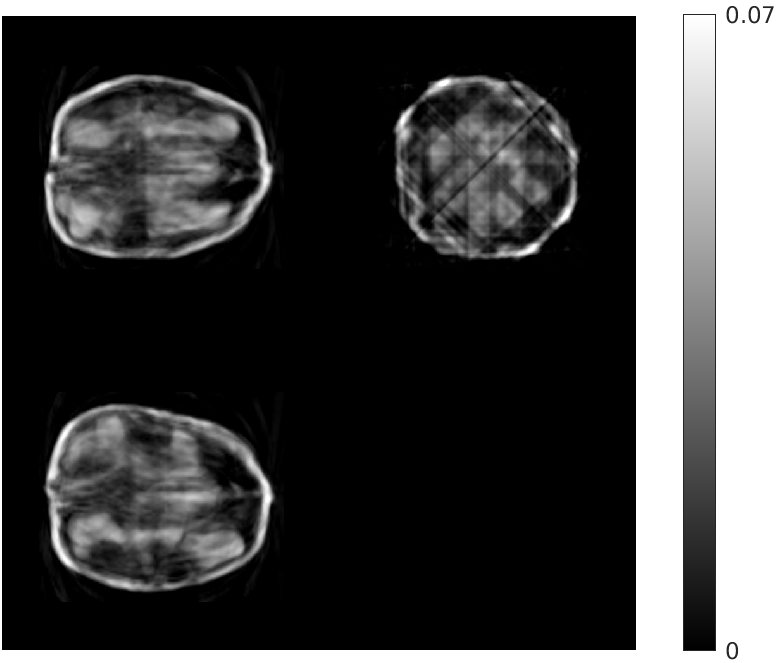

Fig. 4 shows the results of the intermediate steps of the first stage of our reconstruction for walnut 2 (8 views) in the test dataset. While the patch-based destreaking compensates for the blurring introduced by the EP-regularized reconstruction and ‘fills-in’ details in the reconstructed volume, the data-consistency plays a key role in mitigating hallucinations introduced by the CNN, and reinforces image features that are consistent with the acquired measurements.

| Input EP Recon. | Post CNN-based Destreaking | Post Data-consistency |

![]() |

| (NMAE:0.45) | (NMAE:0.38) | (NMAE:0.32) |